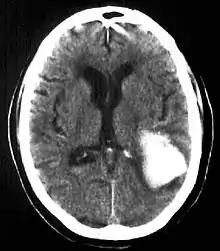

| Multiple intraparenchymal hemorrhage | |